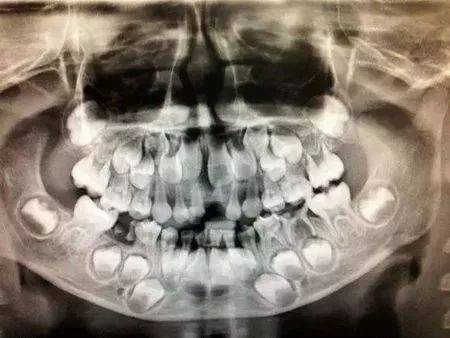

孩子换牙期间的x光片也太恐怖了!下颌骨里藏的全是牙齿,哈哈哈

如上图,透过x光来看到换牙时期颌骨内的情况是这样的.

一个换牙期小朋友的x光全景片